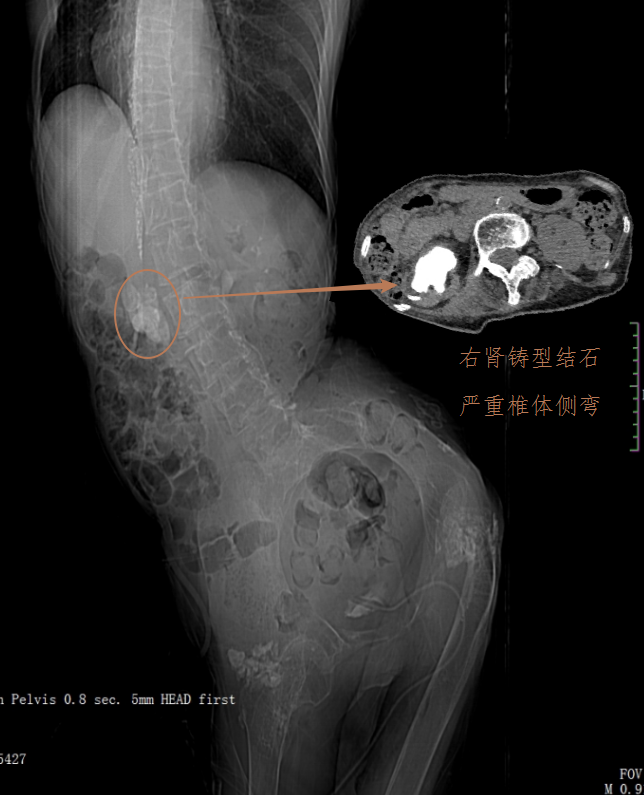

贺奶奶腹部CT图像(肾脏铸型结石,严重的身体畸形)

入院时,医生发现,贺奶奶胸部以下完全没有知觉,由于没有神经支配,腹部和下肢肌肉萎缩僵直,脊柱严重侧弯畸形,身体多处皮肤压疮,深达骨头。同时,这50多年间,老人出现反复的泌尿系统感染,经历2次膀胱切开取石和胆囊切除,但是右边肾脏里面还有一颗巨大的铸型结石却一直没有得到救治)。

后,贺奶奶家人找到了泌尿四科杨科主任,杨科主任收治贺奶奶入院,检查发现其右肾铸型结石导致肾脏几乎无功能,反复的感染导致肾脏至皮肤形成窦道不停流脓,令奶奶的身体雪上加霜。体重只有30公斤的她,营养状态差,又合并着高位截瘫、脊柱侧弯、反复感染以及有多次手术病史,给手术医师增加巨大难度,卧床不动、皮肤压疮、肌肉及神经萎缩给护理增添不少压力。经过一周的严密而又详细的术前评估,杨科主任手术团队从手术体位模拟,切口入路、术中可能发生情况等一条条仔细评估,经过3小时的手术时间顺利完成右肾切除手术,后期经过医护人员的精心护理下,贺奶奶手术后1周顺利出院。